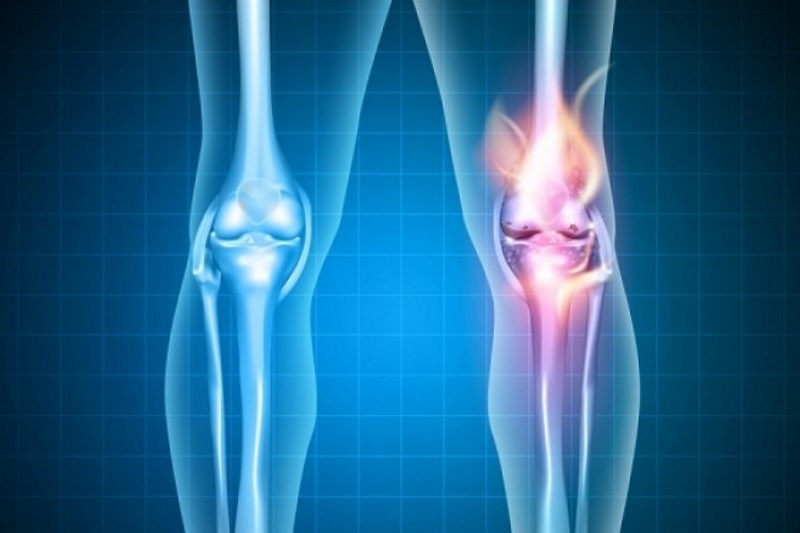

Τροφές και ποτά που προστατεύουν τις αρθρώσεις σου

Η οστεοαρθρίτιδα μπορεί να ξεκινήσει σταδιακά να καταστρέφει τις αρθρώσεις ακόμη και από την ηλικία των 30 ετών.

Ο πόνος στα γόνατα όταν ανεβαίνουμε σκάλες είναι συνήθως η πρώτη ένδειξη οστεοαρθρίτιδας, σύμφωνα με μελέτη που πραγματοποιήθηκε από ερευνητές στο Πανεπιστήμιο του Ληντς.